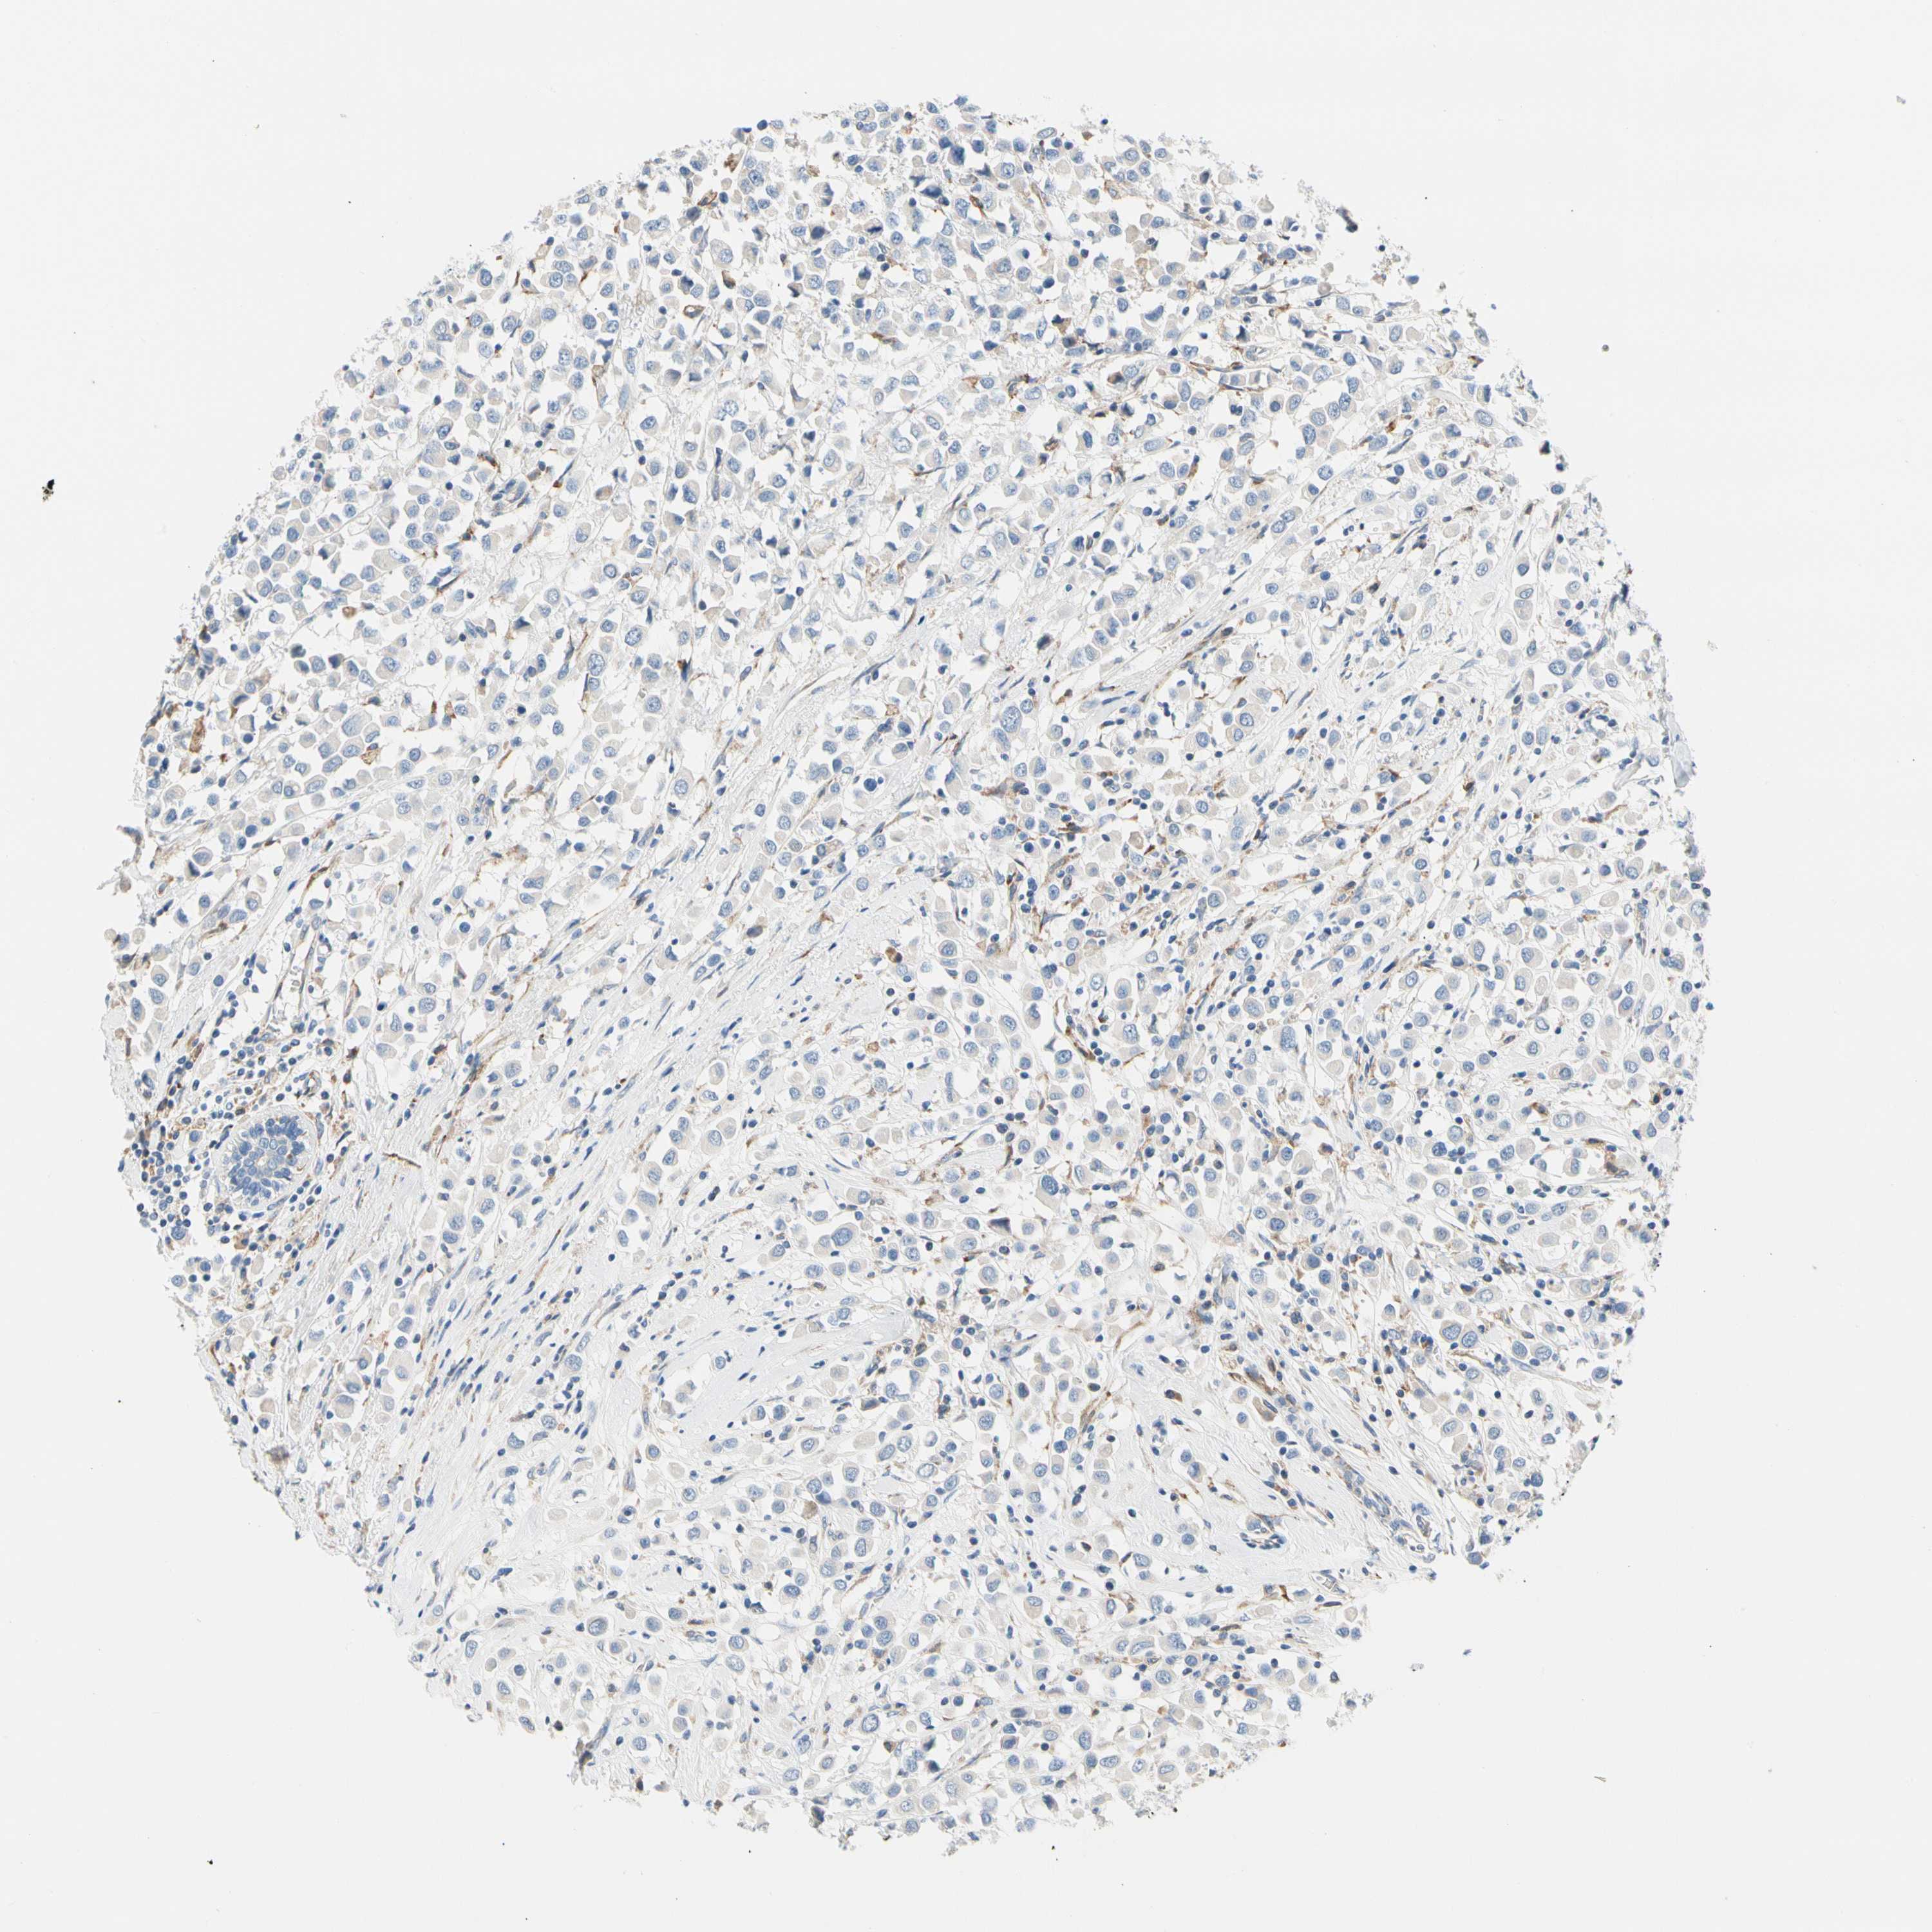

CANCER BREAST CANCER Show tissue menu

BRCA TCGA BRCA VALIDATION PROTEIN EXPRESSION